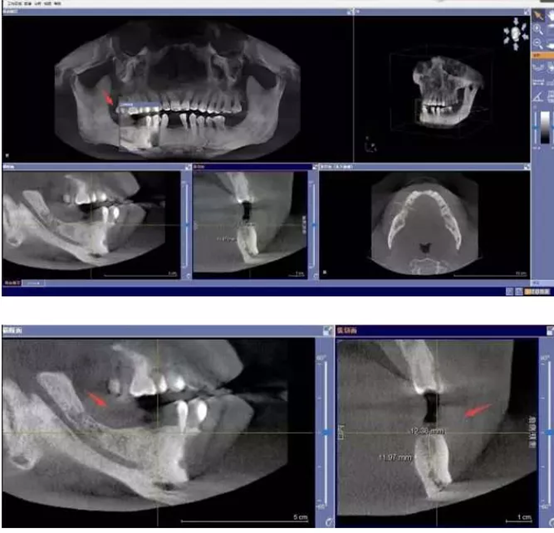

NO.1先要做一个口腔全景片、颌骨CT等医生根据机器成像查看口腔的具体情况,是否有炎症、牙槽骨的密度、吸收状况以及邻牙组织、牙体组织等。

注明:此数据仅作模拟,不是确切种植数据。

如果仅靠双眼大致估测口内数据,是无法得到精准的高度、宽度的,也无法确认骨头吸收多少,是否需要植入骨粉。对后期手术有一定的影响。通过全景片可以“解剖”牙齿精确测量,适宜的种植角度也可确定,健康安全有保障。